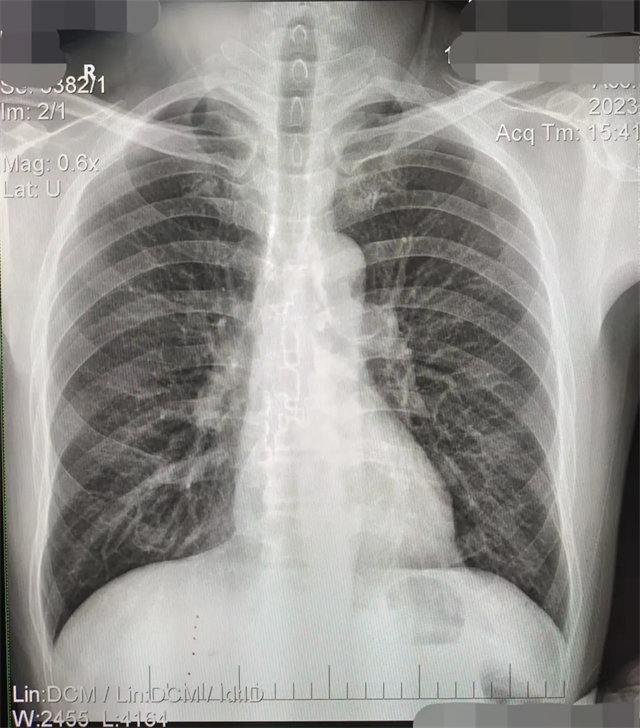

缺陷:肩胛骨未完全拉離肺野,吸氣不完全,存在金屬偽影遮擋,略有聳肩,且肺尖顯示不好,圖像顆粒感較強,管電流量不夠,信噪比偏低。

解決:去除金屬物品后,按標準體位,使患者雙肩旋前與前胸一并緊貼成像件,適當調高mAs,然后深吸氣后屏氣曝光。